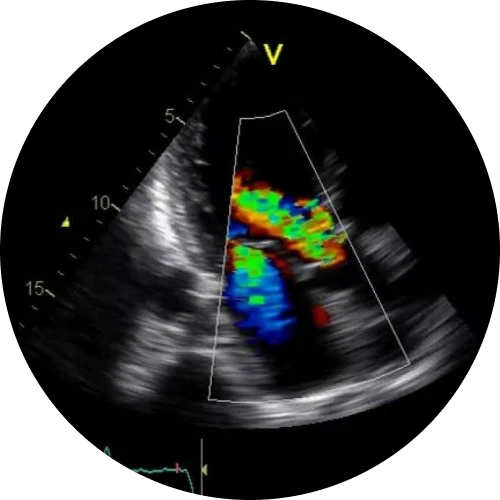

کالرداپلر

مرکز سونوگرافی دکتر سعید صادقی با بهرهگیری از تجهیزات پیشرفته و تکیه بر دانش تخصصی در حوزه تصویربرداری پزشکی، ارائهدهنده طیف کامل خدمات سونوگرافی بزرگسالان و اطفال است. در این مجموعه، انواع سونوگرافیهای عمومی و تخصصی، سونوگرافیهای داپلر رنگی و همچنین خدمات فوقتخصصی تیروئید، سر و گردن، پستان و کبد با دقت بالا و استانداردهای روز انجام میشود. این مرکز با رویکردی دقیق و علمی، سونوگرافیهای بارداری و آنومالی را با حساسیت ویژه برای پایش سلامت جنین ارائه میکند. انجام الاستوگرافی و فیبرواسکن کبد، نمونهبرداری و بیوپسی تودههای سر و گردن، تودههای پستان، ضایعات عضلانی–اسکلتی و نمونهبرداری FNA تیروئید نیز توسط دکتر صادقی با کمترین درد و بیشترین اطمینان انجام میگیرد. علاوه بر این، امکان مشاوره تخصصی در زمینه بررسی و تفسیر CT اسکن و MRI نیز برای بیماران فراهم شده تا مسیر تشخیص و درمان با اطمینان و آرامش بیشتری طی شود. ماموریت ما ارائه تصویربرداری دقیق، پاسخگویی مسئولانه و همراهی صمیمانه با بیماران است.